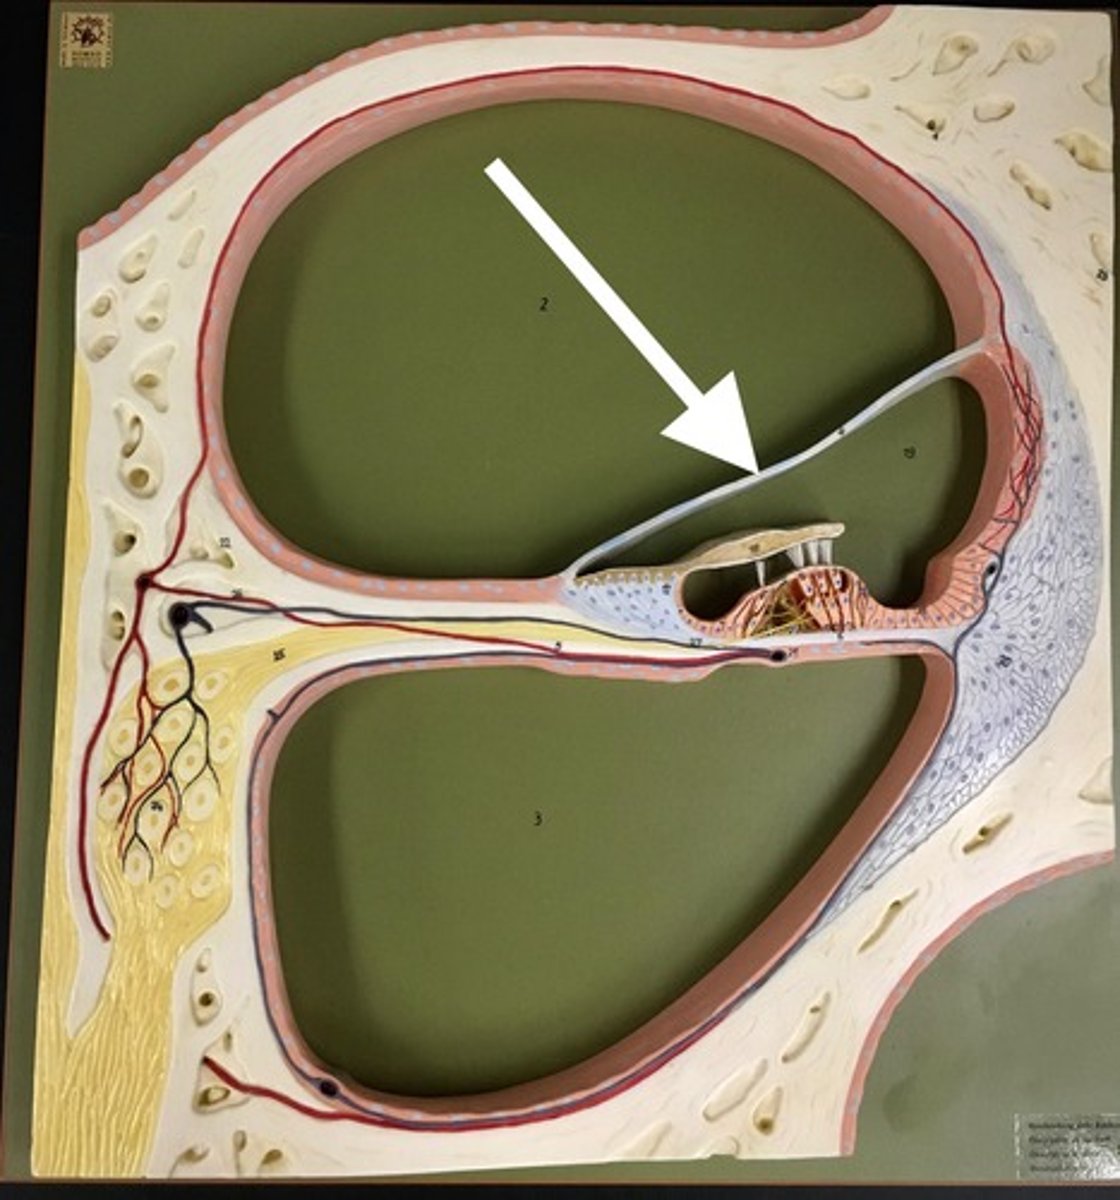

cochlea

a coiled, bony, fluid-filled tube in the inner ear through which sound waves trigger nerve impulses

helicotrema (spiral hole)

the opening that connects the scala vestibuli and scala tympani chambers at the apex of the cochlea.

scala vestibuli/vestibular duct

perilymph-filled top chamber of cochlea. Closest to vestibular system.

scala tympani

perilymph-filled cochlear chamber that connects to the round window

scala media

Middle chamber of the cochlea; filled with endolymph

membranous separation between scala vestibuli and scala media